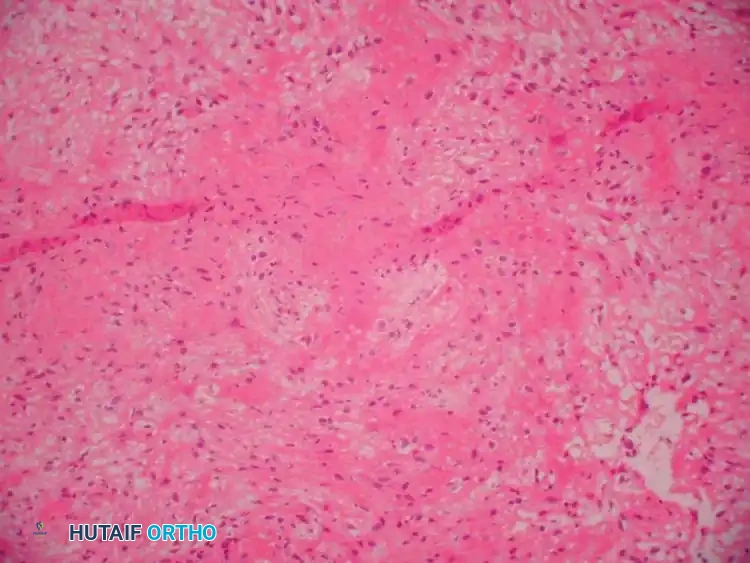

Histopathology

Grossly, an ABC resembles a blood-filled sponge. It is a cavitary lesion partitioned by fibrous septa. Microscopically, the tissue is highly hemorrhagic with cavernous spaces separated by a cellular stroma. The lining of these spaces lacks an endothelial layer (differentiating it from a true vascular tumor) and instead consists of compressed fibroblasts, histiocytes, hemosiderin-laden macrophages, and multinucleated giant cells.